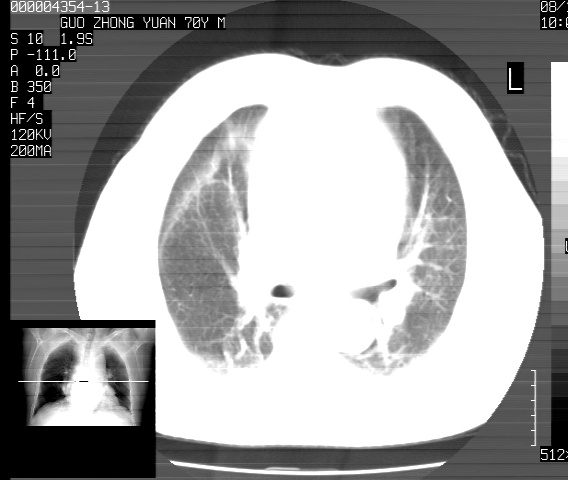

以下是引用sdzyy在2008-12-1 11:49:00的发言:[br]图像不全,请上传,右下肺炎症可能性大,占位待排.

以下是引用zjzjr在2008-12-1 14:53:00的发言:[br]图像不全,请上传,右下肺炎症可能性大,占位待排.心影增大,建议进一步检查.